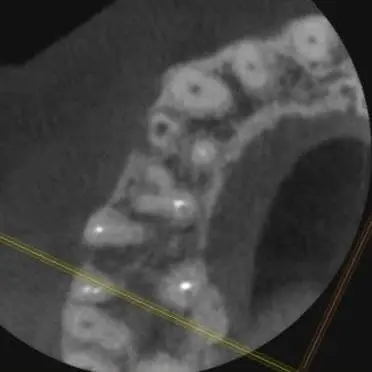

Аксиальный срез (от лат. axis — ось) - это горизонтальный срез КЛКТ, проходящий перпендикулярно длинной оси зуба.

Проще говоря: Это срез "сверху вниз" - как если бы вы смотрели на зуб с окклюзионной поверхности.

Представьте: Вы берёте зуб, разрезаете его горизонтально, смотрите на срез сверху и вот что вы видите:

- Контур коронки зуба (внешняя граница)

- Дентин (серая масса)

- Пульпарная камера (тёмная полость в центре)

- Каналы (тёмные точки/овалы - это просветы каналов)

- Открыла аксиальный срез КЛКТ

- Увидела, что устье ДЩ канала находится на одной линии с устьем МВ2 канала